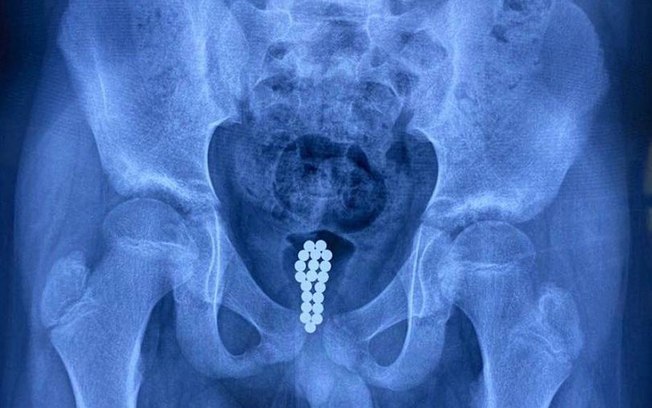

Um garoto de 11 anos sofreu com fortes dores por uma semana depois de colocar 20 bolas magnéticas no próprio pênis.

Honghui realizou uma cistoscopia – uma endoscopia da bexiga – durante a qual ele conseguiu contar os ímãs agora enferrujados no órgão da criança. “Mas como não conseguimos remover uma série de 20 esferas através de uma cistoscopia, optamos por uma cirurgia minimamente invasiva”, disse em entrevista ao site.

O médico observou que a uretra era muito estreita para remover os objetos sem correr o risco de causar mais ferimentos. Mas a cirurgia foi considerada um sucesso.